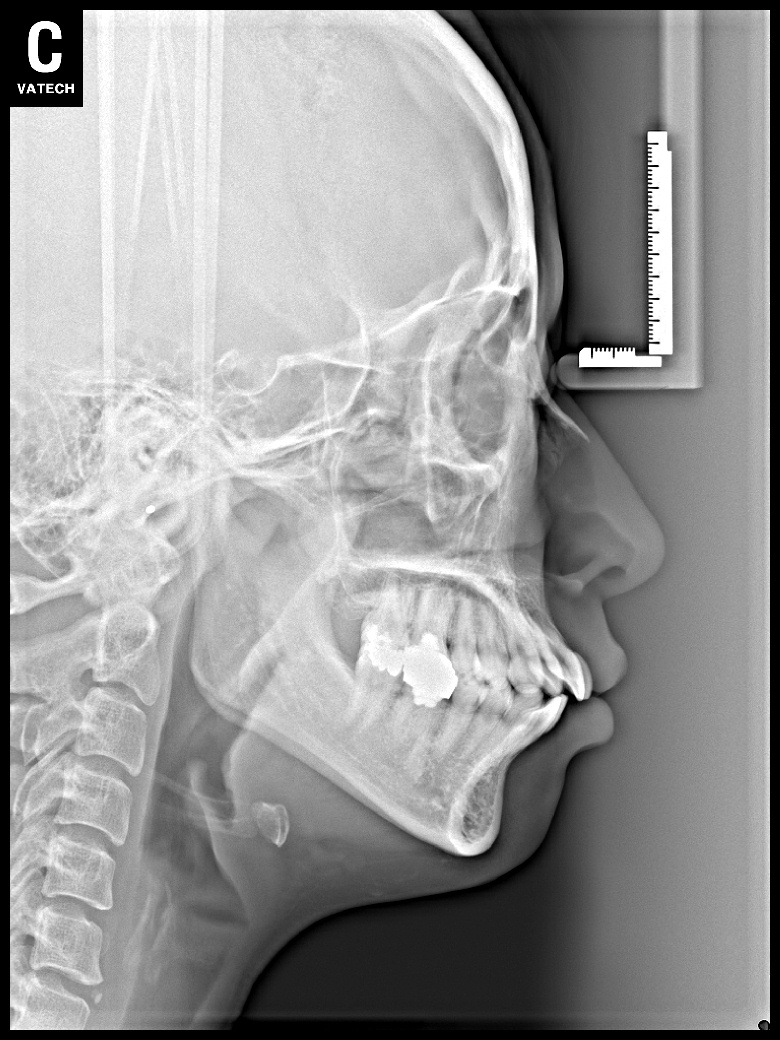

치료 후 사진입니다.